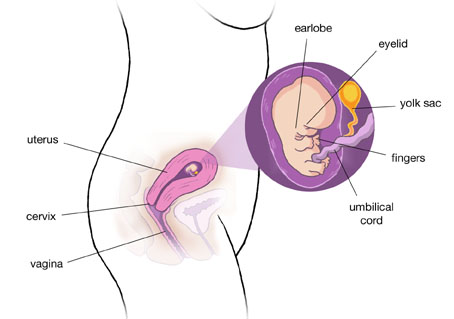

Незважаючи на те, що ваш малюк ще дуже маленький, він вже схожий на чоловічка: при УЗД на цьому терміні вже можна чітко розрізнити його головку і тулуб, розміри яких зараз майже однакові, ручки і ніжки, очі, початківці розвиватися вушка.

Темпи розвитку ембріона зараз просто вражаючі: щодня з ним відбуваються життєво важливі зміни. Його органи починають активно працювати, він отримує харчування через пуповину. На 8 тижні вагітності розмір малюка наближений до виноградині: його вага - близько 3 г, а зріст - 1,5 - 2 сантиметри.

Термін 7-8 тижнів вагітності характеризується формуванням пальчиків на ручках і ніжках малюка. У ембріона ще є хвостик, він поступово починає зникати.

У малюка починають формуватися риси обличчя. Вже є очі, які поки щільно закриті століттями і знаходяться на бічних поверхнях голови. Формуються вушка, губи, можна розрізнити носик, який поки ще закритий.

Ручки і ніжки малюка вже можуть згинатися - формуються великі суглоби. Малюк вже може рухатися.

Матка на 8 тижні вагітності поступово збільшується в розмірах. Зараз вона не перевищує розміри вашого кулачка, але зовсім скоро ви помітите, що животик вже починає округлятися.

Незважаючи на те, що матка ще не дуже велика, ви вже можете відчувати часті позиви до сечовипускання. Деякі майбутні матусі при цьому намагаються обмежити обсяг рідини, що випивається, проте це абсолютно неправильно. За добу ви повинні випивати не менше двох літрів чистої води - це забезпечить нормальний метаболізм, очищення організму від продуктів обміну, освіта необхідної кількості амніотичної рідини.